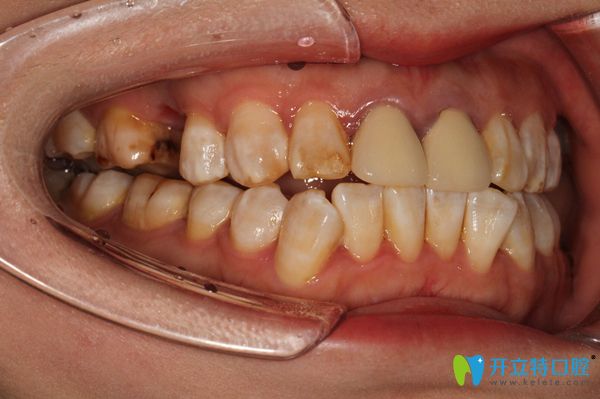

經(jīng)過(guò)了一系列的檢查后,開(kāi)始種植牙手術(shù),醫(yī)生技術(shù)真是嫻熟啊,錢女士感覺(jué)治療過(guò)程沒(méi)幾分鐘就好了,不過(guò)先放入種植體,張醫(yī)生就給錢女士放的是瑞士iti種植體。

戴上種植體后圖片